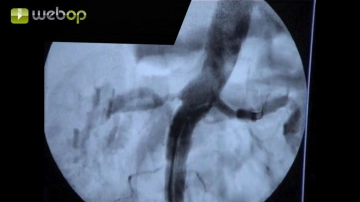

Perkutane Punktion der A. femoralis communis linke Leiste nach Seldinger und Einbringen des Führungsdrahtes. Nach Entfernung der Punktionskanüle wird über den liegenden Führungsdraht eine 6-F-Schleuse unter Durchleuchtungskontrolle eingeführt. Nach Entfernung des Drahts lokale Gabe von 5000 IE Heparin-Kochsalz-Lösung und Überprüfen des pulsatilen Rückstroms.